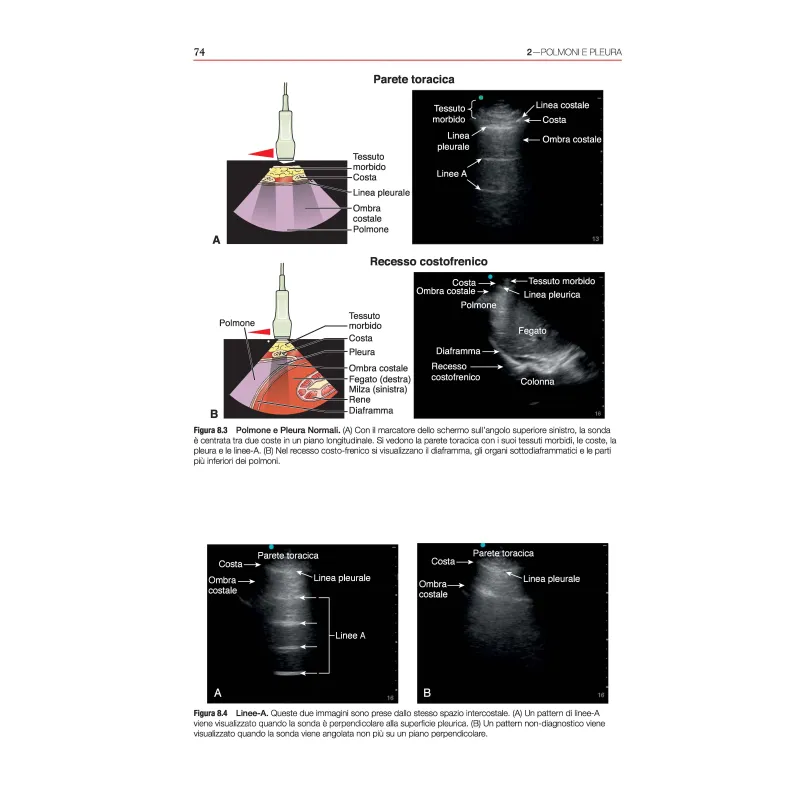

È stato dimostrato che l’ecografia point-of-care (POCUS) rende le procedure più sicure, accelera e aumenta l’accuratezza delle diagnosi e incrementa la sicurezza nel processo decisionale clinico. La POCUS è una delle poche nuove tecnologie che avvicina l’operatore sanitario direttamente al letto del paziente, migliorando così l’esperienza sia dei pazienti che degli operatori sanitari stessi. La prima edizione di Point-of-Care Ultrasound è stata pubblicata nel 2014 e ha posto le basi per la condivisione delle conoscenze tra diversi ambiti specialistici che utilizzano le più diverse applicazioni ecografiche al letto del paziente. Dalla sua prima pubblicazione, il libro è stato tradotto in cinese e spagnolo, con migliaia di copie distribuite in tutto il mondo. Man mano che gli operatori sanitari imparavano a conoscere le potenzialità della POCUS, un numero crescente di essi ha utilizzato questo libro. Data la natura visiva e dinamica dell’ecografia, questo libro mette a disposizione numerosi video. Il suo stile da manuale, i capitoli concisi, le figure esplicative e i suggerimenti di insegnamento pratici sono accattivanti anche per i medici più impegnati che cercano di ampliare le loro conoscenze in materia di ecografia. In questa seconda edizione, abbiamo allargato i contenuti in diversi modi. In primo luogo, abbiamo aggiunto sei nuovi capitoli sull’emodinamica, sull’ecocardiografia transesofagea, sul secondo e terzo trimestre di gravidanza, sulla pediatria, sulla neonatologia e sull’ecografia transcranica. In secondo luogo, abbiamo aumentato i contenuti video online da circa 300 a oltre 1000 video che mostrano gli aspetti ecografici normali e patologici. In terzo luogo, abbiamo aggiunto nuovi casi clinici e domande di verifica alla fine di ogni capitolo, sottolineando i punti chiave dell’apprendimento. Infine, ci siamo tenuti al passo con questo campo in rapida evoluzione aggiornando la letteratura, le immagini e le figure in ogni capitolo. I princìpi e le ampie applicazioni della POCUS sono trattati in modo dettagliato. Siamo certi che gli operatori sanitari di qualsiasi ambito che desiderino imparare la POCUS saranno soddisfatti da questa seconda edizione del nostro libro.